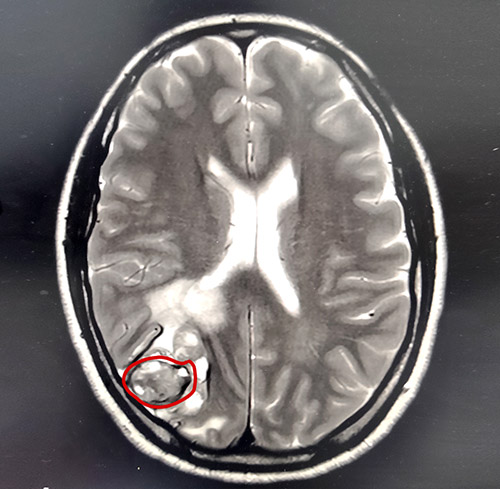

胡女士就是不信這個邪,經(jīng)多方打聽后胡女士輾轉(zhuǎn)來到上海藍十字腦科醫(yī)院。在藍十字腦科醫(yī)院進行了仔細全面的體檢,影像檢查提示:左足跟黑色素瘤切除術后,患者顱腦右側(cè)枕葉皮髓質(zhì)交界處高密度團塊伴周圍腦實質(zhì)水腫,考慮為轉(zhuǎn)移瘤。身體其他部位未見明顯轉(zhuǎn)移灶。

▲MRI提示右側(cè)頂枕葉皮髓質(zhì)交界處占位

基于細致嚴謹?shù)臋z查評估后,上海藍十字腦科醫(yī)院神經(jīng)外科主任沈建康教授領銜的專家團隊一致認為,手術切除患者腦部腫瘤具備條件,且可有效延長患者生存期,提高生存質(zhì)量。